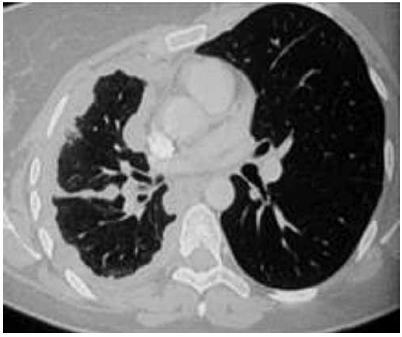

Paciente de 19 anos procura unidade básica de saúde

com queixa de dor em região anterior de hemitórax

esquerdo. Fez radiografia e tomografia, apresentadas a

seguir. Foi submetido a biópsia transtorácica, que revelou

neoplasia maligna com padrão morfológico de pequenas

células redondas e azuis (HE).

(Arquivo pessoal; imagem usada com autorização)

Perfil imuno-histoquímico:

• Positivo para SALL-4, Glypican e citoqueratinas Ae1/ Ae3.

• Negativo para CD 117; CD 30; p40 e PAX-8; CD 10; TdT e CD 99; CD 3; PAX-5 e CD45.

• Imunoexpressão para Ki-67 revela índice de proliferação de 40%.

De acordo com o caso clínico e o resultado anatomopatológico, é correto afirmar que se trata de tumor do tipo